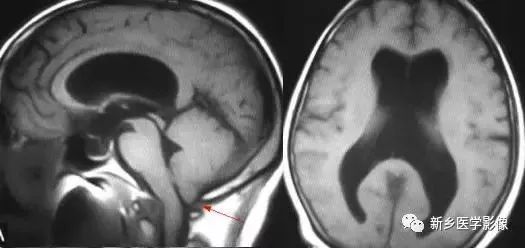

前脑无裂畸形(holoprosencephaly):

是指一系列位于中线程度不同的畸形,累及大脑、面部、脑于和小脑。前脑未能够分开,呈不全性或完全性,端脑和间脑无法区分。根据脑及面部畸形程度将其分为无叶型、半叶型和单叶型。

- 无叶型前脑无裂畸形:最严重,端脑半球间没有裂隙,呈马蹄形或新月形扩大的单脑室跨越中线,与背侧囊交通。丘脑互相融合,面部畸形可有两眼距离过近、独眼畸形等。往往死于胎儿或新生儿期。

- 半叶型前脑无裂畸形:在前脑可见部分裂隙, 形成不同发育程度的大脑纵裂及大脑镰。两侧大脑半球在前部未完全分开,但枕叶和 双侧侧脑室体部分离,丘脑分开不完全。三脑室和海马发育不全,胼胝体仅可见到压部,而其他部分缺如额叶和基底节前部分辨不清。临床表现有两眼距离过近、唇裂、腭裂等面部畸形,侧脑室呈单一性且明显扩大。

- 单叶型前脑无裂畸形:与正常发育脑仅有些很小的区别,如透明隔缺如或双侧额叶不完全分开。